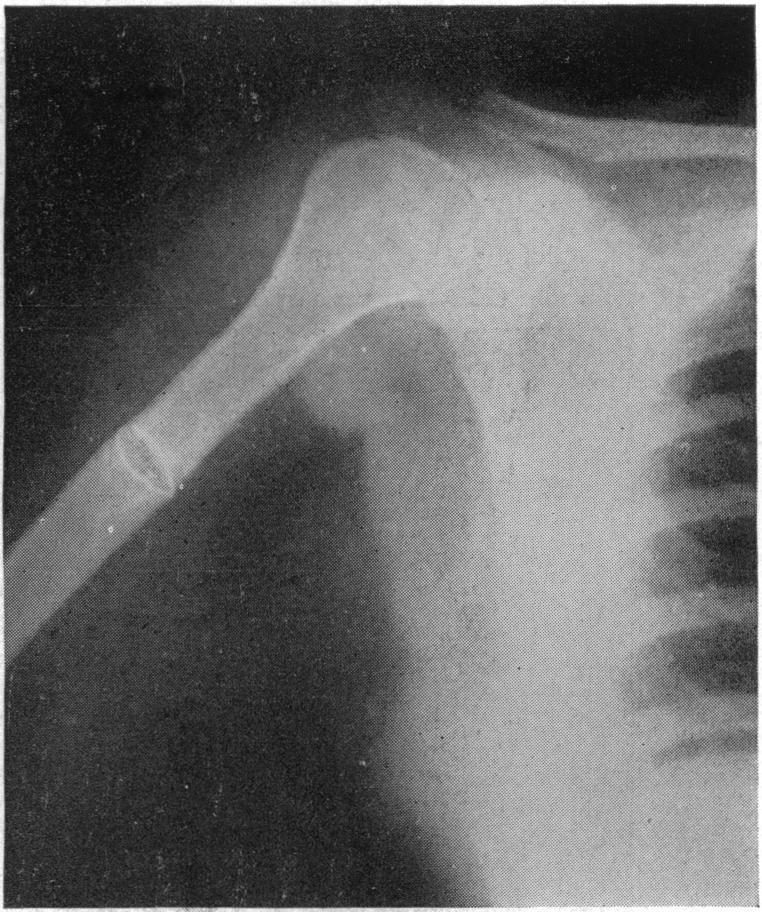

Reverse vascularized bone graft of the lateral distal humerus for non-union of the radial neck fracture: anatomical study and case report.

J Plast Surg Hand Surg. 2019 Feb;53(1):20-24. doi: 10.1080/2000656X.2018.1520122. Epub 2019 Jan 12.